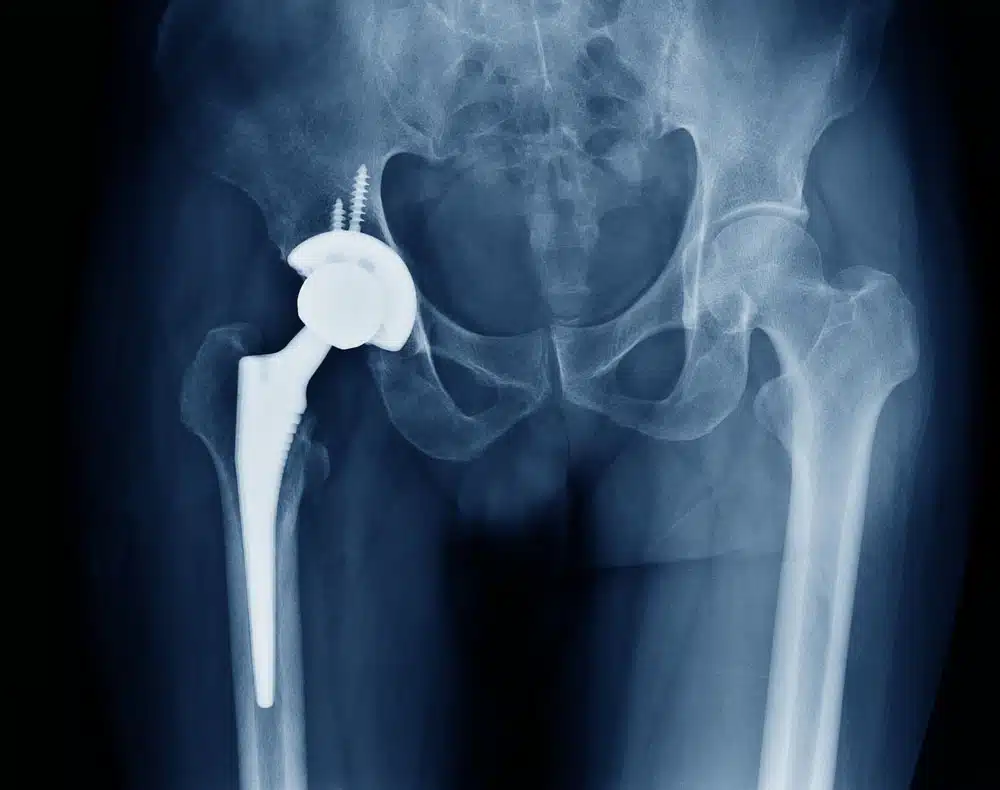

جراح ارتوپد سپس کاسه فلزی یا پلاستیکی را داخل حفره تراشیده استابولوم قرار می دهد و یک سر فلزی را داخل بخش باقیمانده گردن استخوان فمور قرار می دهد تا در مجموع با اتصال به هم مشابه یک مفصل کامل عمل کنند. این مفصل مصنوعی لگن در محلش ثابت می شود.

سر فلزی مفصل مصنوعی توسط یک بخشی بنام دسته استم به باقیمانده گردن فمور متصل می شود و جراح ارتوپد سر فلزی را با ورود آن به داخل کانال مرکزی استخوان ران محکم می کند.

بطور کلی در یک عمل جراحی تعویض مفصل لگن، بخش آسیب دیده مفصل لگن خارج و با یک بخش مصنوعی یا پروتز جایگزین می گردد. پروتز لگن معمولا از یک تنه تشکیل شده که استخوان لگن را به استخوان ران وصل می کند. همچنین از یک کاپ تشکیل شده که داخل مفصل لگن قرار می گیرد. جنس این تنه و کاپ از نوعی فلز (وگاهی پلاستیک یا سرامیک) می باشد، در حالی که جنس بخش مفصلی سرامیکی است.

بطور کلی پروتز لگن 2 نوع مختلف دارد: پروتزهای سیمانی و پروتزهای غیر سیمانی.

پروتزهای غیر سیمانی توسط یک سطح ویژه ای به استخوان وصل می شوند. به عبارت دیگر یک سر پروتزهای غیر سیمانی به داخل کانال استخوان ران محکم شده و سر دیگر پروتز داخل مفصل لگن قرار می گیرد. در پروتزهای سیمانی، از یک چسب جراحی برای اتصال پروتز به مفصل استفاده می گردد.